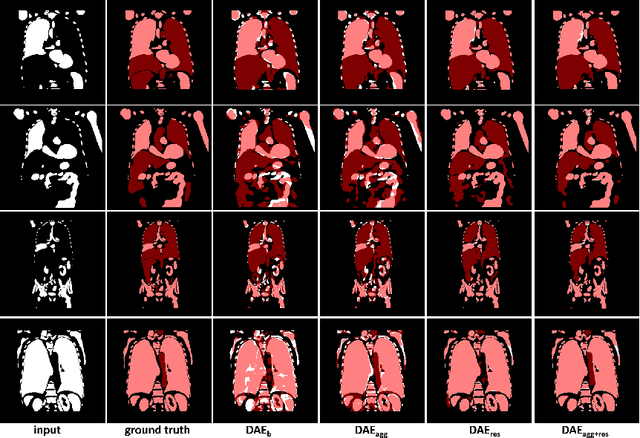

Abstract:In this paper, we introduce a completion framework to reconstruct the geometric shapes of various anatomies, including organs, vessels and muscles. Our work targets a scenario where one or multiple anatomies are missing in the imaging data due to surgical, pathological or traumatic factors, or simply because these anatomies are not covered by image acquisition. Automatic reconstruction of the missing anatomies benefits many applications, such as organ 3D bio-printing, whole-body segmentation, animation realism, paleoradiology and forensic imaging. We propose two paradigms based on a 3D denoising auto-encoder (DAE) to solve the anatomy reconstruction problem: (i) the DAE learns a many-to-one mapping between incomplete and complete instances; (ii) the DAE learns directly a one-to-one residual mapping between the incomplete instances and the target anatomies. We apply a loss aggregation scheme that enables the DAE to learn the many-to-one mapping more effectively and further enhances the learning of the residual mapping. On top of this, we extend the DAE to a multiclass completor by assigning a unique label to each anatomy involved. We evaluate our method using a CT dataset with whole-body segmentations. Results show that our method produces reasonable anatomy reconstructions given instances with different levels of incompleteness (i.e., one or multiple random anatomies are missing). Codes and pretrained models are publicly available at https://github.com/Jianningli/medshapenet-feedback/ tree/main/anatomy-completor